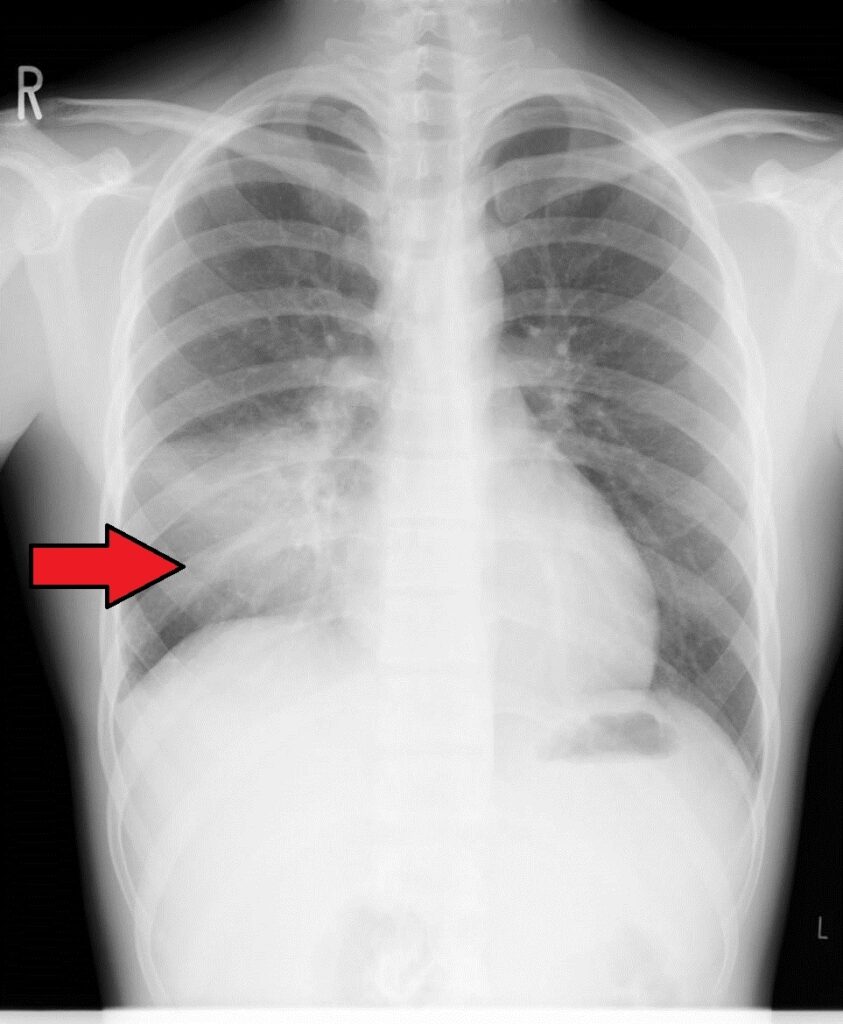

肺炎になるとレントゲン上でも白く影が見えてくることが多いですが、気管支炎では影が見えることはあまりありません。